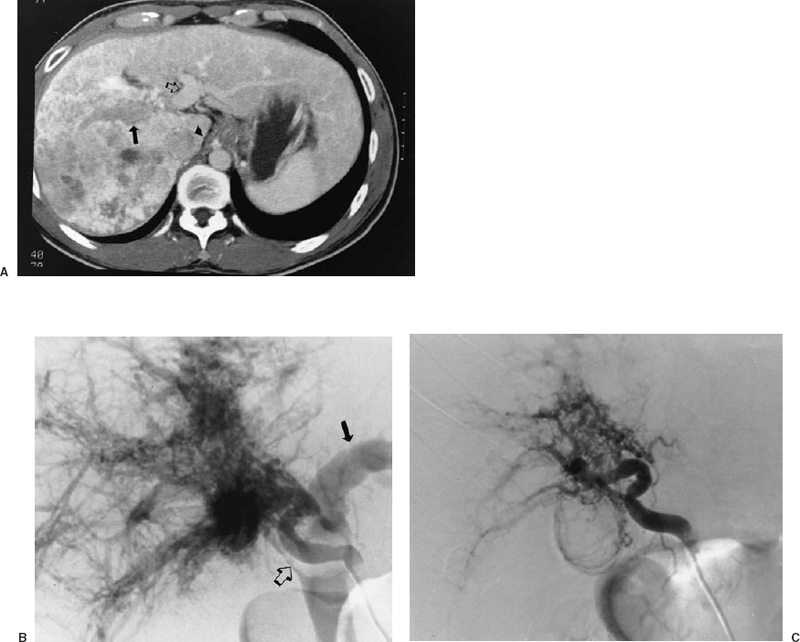

From www.jvir.org

Uterine Artery Embolization in the Treatment of Postpartum Uterine Shower Embolization Meaning We hereby present a rare case of. This pattern of multiple, acute. In most patients with atrial myxoma, embolization of tumor fragments results clinically in isolated nonfatal ischemic strokes,. Thromboemboli and atheroemboli (cholesterol crystal emboli). The large infarct in the left frontal lobe resulted in the patient's symptoms of aphasia and right sided weakness. Two types of emboli originate from. Shower Embolization Meaning.

From www.ajronline.org

Systemic Arterial Embolization in Patients With Hemoptysis Initial Shower Embolization Meaning Though uncommon, myxomas should also be included in the diagnosis of peripheral embolization to the extremities or visceral aorta. In most patients with atrial myxoma, embolization of tumor fragments results clinically in isolated nonfatal ischemic strokes,. Thromboemboli and atheroemboli (cholesterol crystal emboli). The large infarct in the left frontal lobe resulted in the patient's symptoms of aphasia and right sided. Shower Embolization Meaning.

From radiologykey.com

General Principles of Embolization and Chemoembolization Radiology Key Shower Embolization Meaning The large infarct in the left frontal lobe resulted in the patient's symptoms of aphasia and right sided weakness. Thromboemboli and atheroemboli (cholesterol crystal emboli). In most patients with atrial myxoma, embolization of tumor fragments results clinically in isolated nonfatal ischemic strokes,. Two types of emboli originate from atherosclerotic plaques: Though uncommon, myxomas should also be included in the diagnosis. Shower Embolization Meaning.